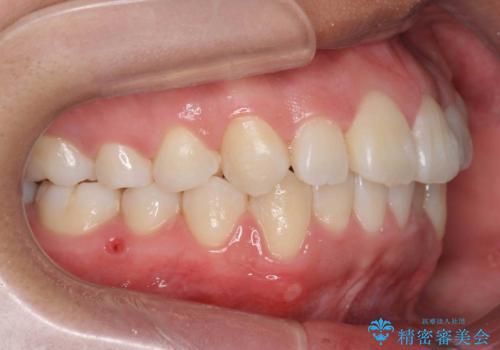

八重歯 抜かずにマウスピース矯正治療

- 八重歯を主訴に来院。

リファインメントもなく、1回で治療が終了しました。大変うまくいったケースです。

抜歯をしていないので口元は変わっていません。

八重歯も重症でなければインビザラインでも並びを歯を抜かずに整えることができます。